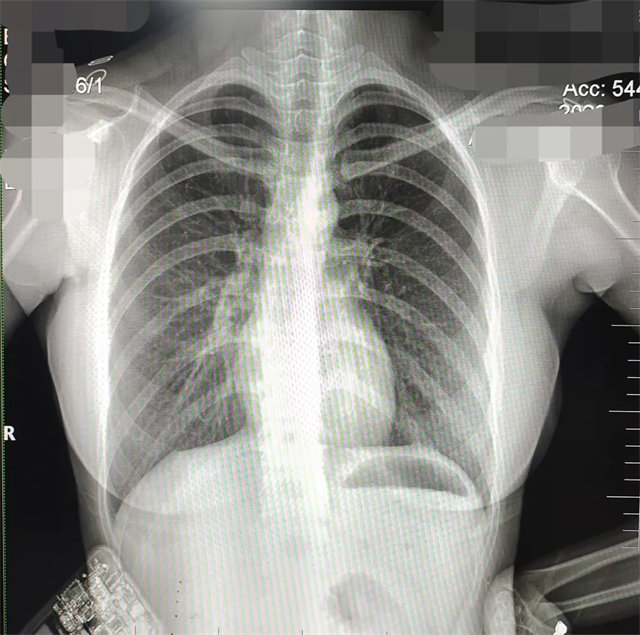

缺陷:左肩胛骨部分与左肺野重叠。

解决:使患者左肩旋前紧贴成像件重新曝光。